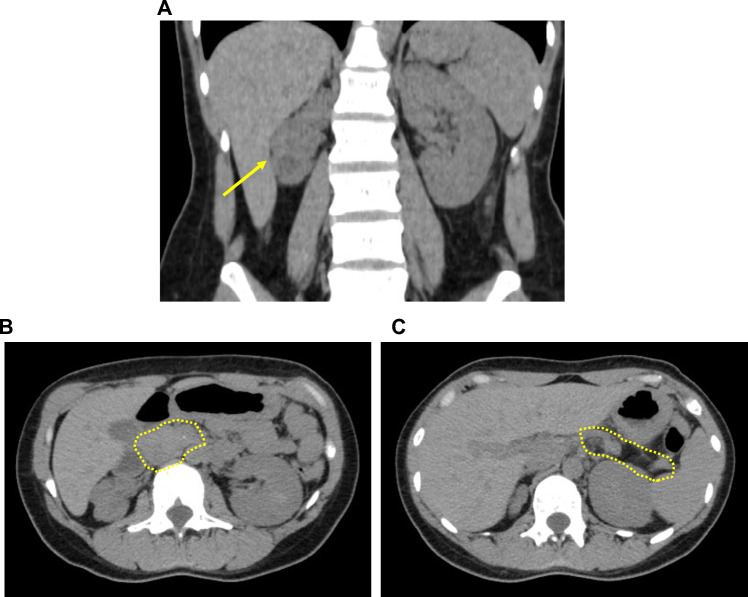

Maturity-onset diabetes of the young type 5 (MODY5), causally associated with loss-of-function of the HNF1B gene, is a rare form of monogenic diabetes that has been underdiagnosed in part because microdeletions of chromosome 17q12 encompassing the HNF1B gene cannot be detected by sequencing-based approaches, which accounts for about 50% of MODY5 cases. We herein describe a 37-year-old Japanese woman who manifested diabetic ketosis at the onset. The coexistence of features associated with MODY5, including abnormal renal function, impaired insulin secretion, pancreatic hypoplasia and hypomagnesemia, prompted us to decode her genomic information using whole-exome sequencing, where we were not able to identify any pathogenic HNF1B gene mutations. We further examined her genomic integrity using multiplex ligation probe amplification (MLPA) analysis, leading to identification of the 17q12 microdeletion which was further supported by array comparative genomic hybridization (array-CGH). Her insulin secretory capacity was insufficient, whereas her total daily dose of insulin was 11 U/day (0.25 U/Kg/day), indicating that she was relatively sensitive to insulin. As a possible explanation, we found that her plasma glucagon level was below the detection limit. Since inactivation of acetyl-CoA carboxylase 1 (ACACA), encoded in close proximity to the HNF1B gene, was reported to blunt glucagon secretion, the concurrent deletion of the ACACA gene may be in part responsible for this manifestation. In conclusion, the genetic analyses of MODY5 cases require the judicious use of appropriate genetic technologies. In addition, alpha-cell dysfunction may at least in part account for the variable clinical manifestations of MODY5.